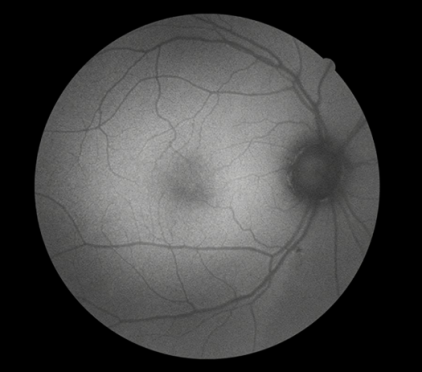

FFA是20世紀(jì)60年代發(fā)展的一項技術(shù)。1961年Navotny 和Alvis首次成功地用膠片記錄到熒光素流經(jīng)視網(wǎng)膜和脈絡(luò)膜血管的動態(tài)過程,開創(chuàng)了眼底熒光血管造影的臨床應(yīng)用時代。如今,F(xiàn)FA主要用于觀察視網(wǎng)膜血管及其血液循環(huán)狀態(tài),高清晰攝像技術(shù)能動態(tài)捕捉視網(wǎng)膜毛細(xì)血管的循環(huán)狀態(tài),間斷或連續(xù)采集可形成視網(wǎng)膜靜態(tài)的黑白圖像或動態(tài)圖像,在診斷中敏感性強,確診率高,能發(fā)現(xiàn)檢眼鏡或眼底照相下不易發(fā)現(xiàn)的視網(wǎng)膜深層微血管瘤,是判斷視網(wǎng)膜病變的“金標(biāo)準(zhǔn)”。

FFA影像